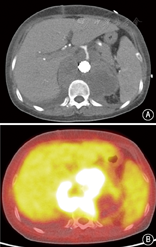

患者女,35岁,因发作性腰背疼痛1年,加重2个月余,于2014年12月入住北京协和医院。患者于2013年12月中旬无明显诱因出现头痛、心慌、大汗,无恶心、呕吐,未重视。2014年1月,患者因头痛伴血压明显升高至200/110 mmHg(1 mmHg=0.133 kPa)就诊于外院,左肾肾小球滤过率(GFR) 7.48 ml/min,超声提示左肾明显萎缩,大动脉造影显示左肾动脉起始段假性动脉瘤形成,压迫左肾动脉导致远端不显影;遂行左侧无功能肾切除术。术后病理提示左侧肾盂组织慢性炎,左肾组织间质少许慢性炎细胞浸润并玻璃样变性,左输尿管残端黏膜组织慢性炎。2014年4月,患者突发少尿,血肌酐(Cr) 795 μmol/L,考虑急性肾功能衰竭,开始行肾脏替代治疗,腹部增强CT提示L1水平腹主动脉左侧动脉瘤,大小约1.9 cm×1.7 cm,右肾动脉闭塞,右肾实质未见异常,腹膜后肿大淋巴结,腹主动脉周围可见软组织密度影包绕,增强扫描未见明显强化(图1A)。肾动脉造影提示右肾动脉主干仅线形显影,余完全闭塞。2014年5月尝试行右肾自体肾移植术,但术中发现肾动脉及其分支全部堵塞,遂切除右肾。术后病理显示右肾脏动脉间叶组织肿瘤,结合免疫组化染色符合血管内膜肉瘤,可见右肾脏肾小球及肾小管透明变性、凝固性坏死伴灶状炎细胞浸润及间质纤维结缔组织增生,右输尿管残端及右肾周脂肪组织未见肿瘤组织(图2);免疫组化:波形蛋白(Vimentin)(+),肌动蛋白(actin)(+),增殖指数(Ki-67)(+,约10%),簇分化抗原(CD)31、CD163、CD68、CD3、白细胞共同抗原(LCA)、B细胞淋巴瘤白血病基因-2(BcL-2)、CD34、高分子量钙调结合蛋白(h-Caldesmon)、平滑肌肌动蛋白(SM-actin)、CD21、CD35、D2-40、CD123、CD20、S-100、第Ⅷ因子相关抗原(FⅧ-RAg)、结蛋白(Desmin)、间变性淋巴瘤激酶(ALK)、CD99、角蛋白(CK)、上皮膜抗原(EMA)、CK18、黑色素瘤相关抗原(HMB45)均(-);未进行后续辅助治疗。2014年7月,患者复查胸腹部CT血管造影(CTA),提示腹膜后肿物包绕T12、L1椎体水平腹主动脉、腹腔干及双肾动脉残端,左肾动脉残端瘤样扩张,大小约2.3 cm×2.1 cm×2.3 cm;患者未治疗。2014年12月3日,患者因腰部剧烈疼痛复查肾动脉超声提示腹主动脉瘤可能性大,大小约5.7 cm×4.0 cm,左肾动脉主干受压前移。当日夜间,患者血压最高达190/110 mmHg,次日早晨患者因失血性休克急诊行大动脉造影提示左肾动脉残端假性动脉瘤(图1B),考虑左肾残端动脉瘤破裂出血,遂行腹主动脉假性动脉瘤腔内隔绝术,术中对支架行肠系膜上动脉开窗。2015年1月,患者上厕所时突发右侧腰背部持续钝痛;腹主动脉CTA考虑腹主动脉假性动脉瘤形成。主动脉造影提示原主动脉支架上方造影剂轮廓不规则,考虑主动脉假性动脉瘤形成(图1C),遂再次行腔内隔绝术,支架放置于腹腔干上方。术后行PET/CT提示腹主动脉(T10~L2水平)周围巨大肿块,包裹腹腔干及肠系膜上动脉,范围约11.8 cm×9.0 cm×10.0 cm,考虑恶性病变,全身其余部位未见明确转移(图3)。出院后患者未行辅助治疗。2015年3月,患者因心力衰竭去世。

病理是诊断该病的金标准。血管内膜肉瘤的影像学表现常不特异,但可协助鉴别内膜肉瘤与其他动脉管腔内占位性病变。该病好发于大动脉,超声常难以探及,且难以鉴别其与血栓或动脉粥样硬化性斑块。增强CT可显示管腔内占位病变、动脉瘤、假性动脉瘤或远处转移灶,但因内膜肉瘤常无明显强化,且可出现动脉壁钙化,故极难与动脉粥样硬化鉴别[7]。目前认为钆增强MRI是诊断该病较好的手段,肿物边缘强化,可为分叶状长T1、长T2信号,可与动脉粥样硬化性斑块、血栓机化等良性病相鉴别[7,8,9]。此外,内膜肉瘤易出现骨转移,因此当怀疑该病时应早期完善全身骨扫描、PET/CT等全身筛查[10]。结合本例患者血管内膜肉瘤部位标准摄取值(SUV)明显升高,因此PET/CT对难以明确性质的血管腔内占位亦有重要诊断价值。